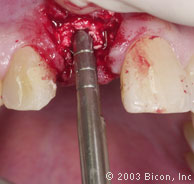

14. | 用2.0mm的先锋钻在1100RPM的转速下预备牙槽骨。 |

15. | 用2.5mm的电动扩孔钻在50RPM的转速下扩大成形,无需冷水降温。 |